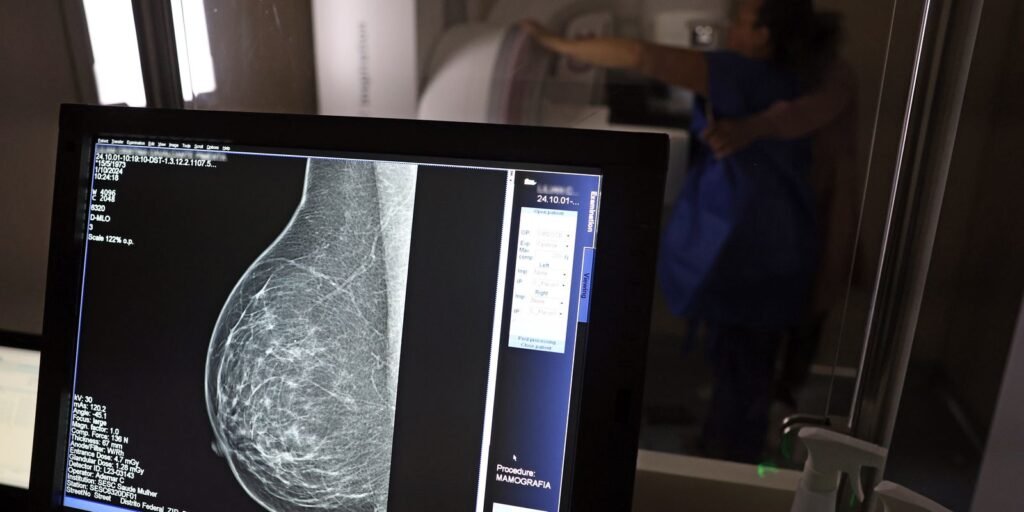

Ministério da Saúde passa a recomendar mamografia a partir dos 40 anos

O Ministério da Saúde passou a recomendar o acesso a mamografia, via Sistema Único de Saúde (SUS), para mulheres de